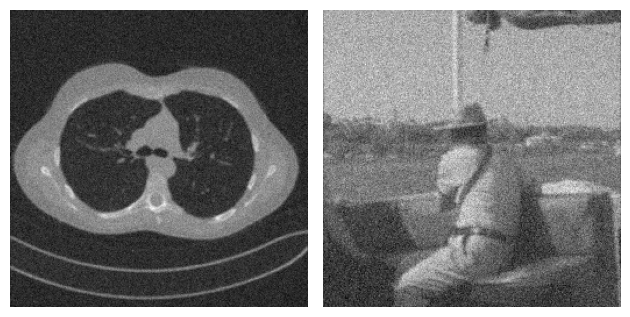

For example, consider the following problem, where two images coming from two completely different datasets are corrupted by Gaussian blur and noise. By looking at both the true image and the corrupted image, it is clear that the content of the two examples is very different. On the other hand, when we look at the residual, i.e. the value \(|x_{true} - y^\delta|\), the patterns in the two images look similar.

This observation justifies that learning the residual is usually easier (and generalizes better) than learning the actual image.